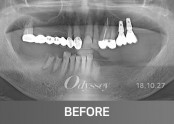

임플란트 181210